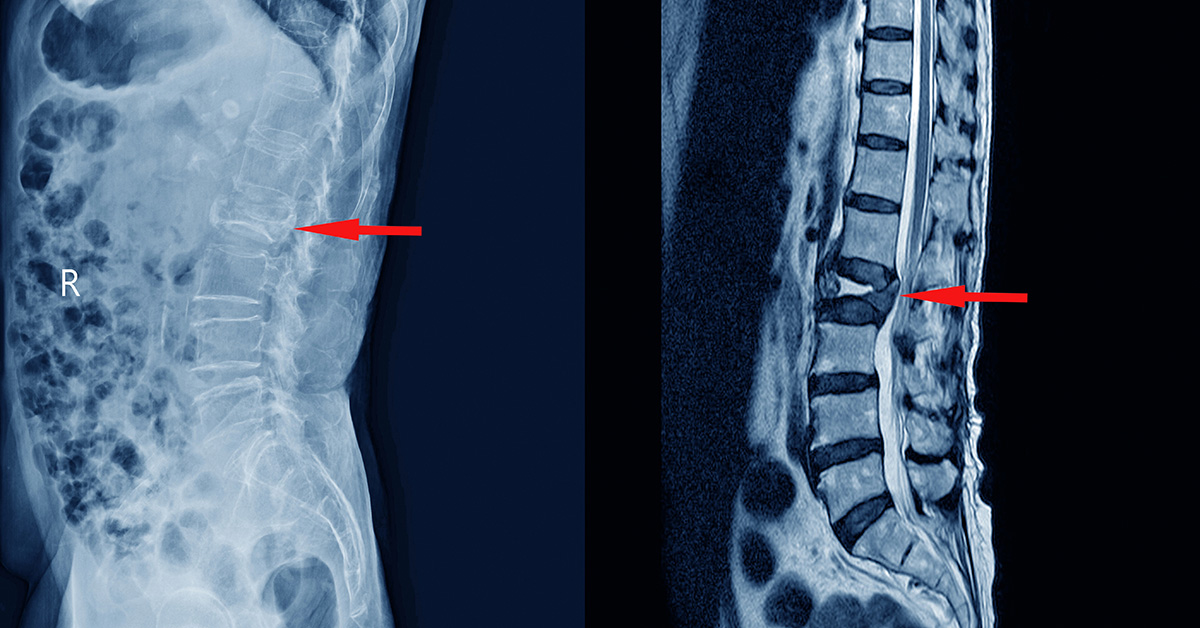

A lumbar laminectomy is a common surgical procedure performed to relieve pressure on the spinal nerves in the lower back. It is most often recommended for conditions such as lumbar spinal stenosis, herniated discs, or bone spurs that cause leg pain, numbness, weakness, or difficulty walking. Because walking problems are a major reason patients seek this surgery, one of the most common questions is whether normal walking can return afterward.

A laminectomy works by removing the portion of bone and soft tissue that is compressing the nerves, allowing them to function more normally.